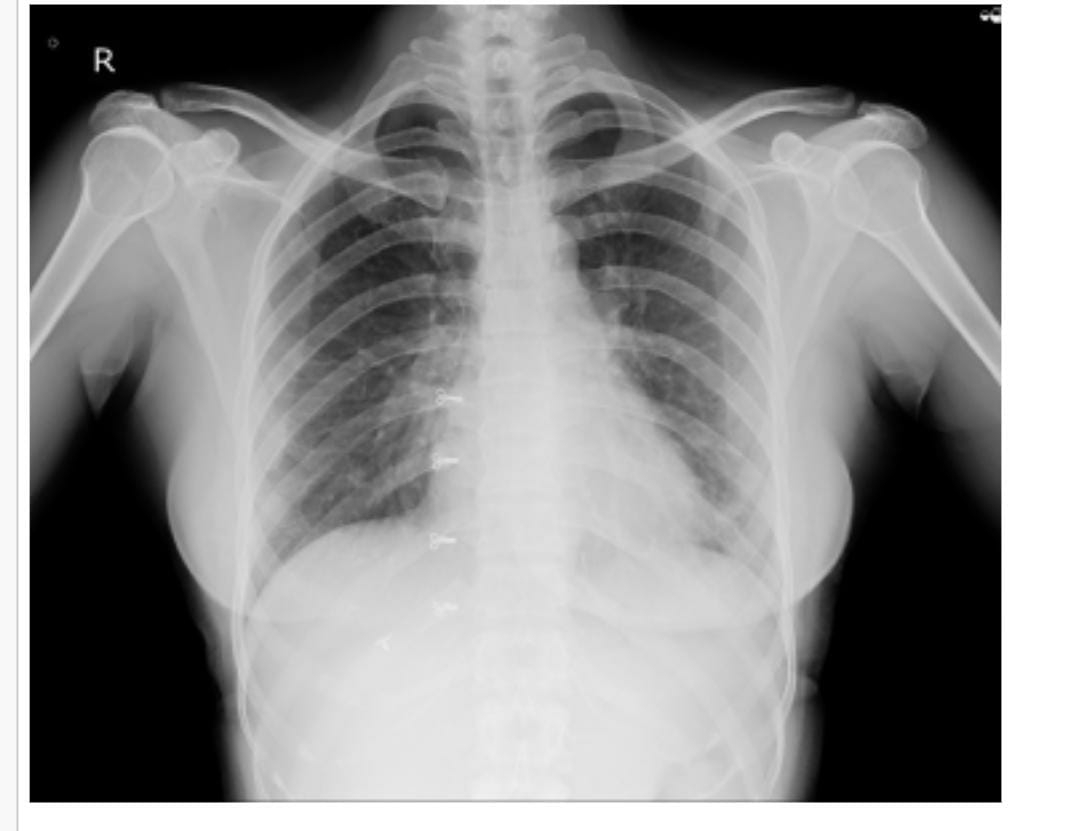

CHEST X RAY: